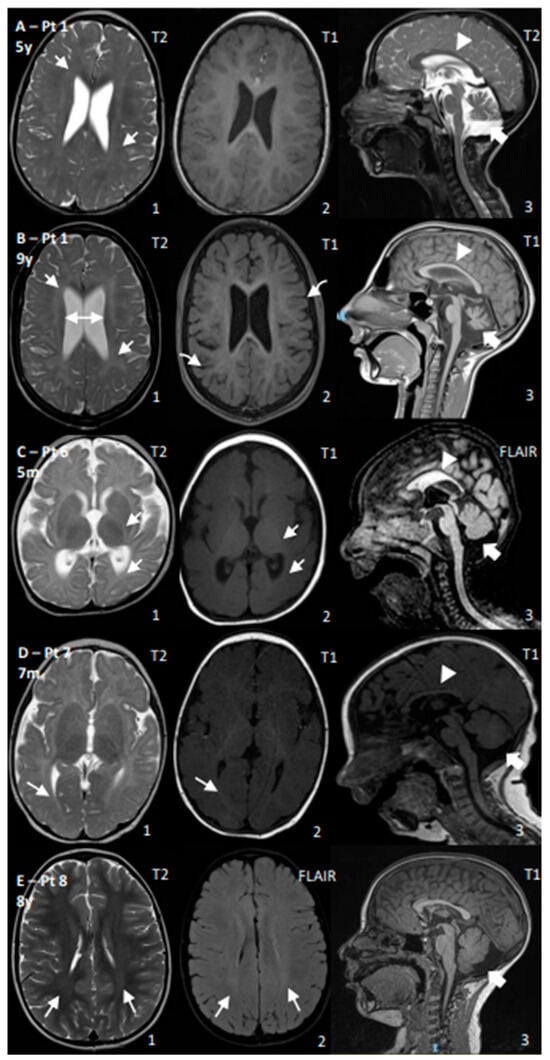

| 1 | CS I | Yes | Yes | No | Yes, −4 SD | Walk (2 y, lost 3 y) | Poor | 45 | Age: 4 y and 9 y: Progressive cerebral and cerebellar atrophy; thin CC; permanent hypomyelination | ERG: normal; VEP: increased latency; BAEP: increased I–V latency; SSEP: increased CCT |

| 2 | CS I | Yes | Yes | No | Yes, −3 SD | Walk with support (2 y) | Poor | 99–136 | Age: 10 m and 1.5 y: Progressive cerebral and cerebellar atrophy; thin CC; WM reduction and hypomyelination | NCV: normal |

| 3 | CS I | Yes | Yes | No | Yes, <−5 SD | Walk with support (1.7 y) | Poor | N/A | Age: 4 y: Permanent hypomyelination | ERG: reduced amplitude |

| 6 | CS II | Yes | Yes | Yes | Yes, <−5 SD | No acquisition | No acquisition | N/A | Age: 5 m: Cerebral, cerebellar, CC, and WM reductions; reduced myelination for age | EEG: occipital anomalies; VEP: poor cortical definition; BAEP: increased I–V latency |

| 7 | CS II | Yes | Yes | No | Yes, <−5 SD | Head control (5 m) | Poor, then regression | 198–270 | Age 7 m: Cerebral, cerebellar, CC, and WM reductions; reduced myelination for age | NCV: demyelinating SM neuropathy; ERG: normal; VEP: high latency |

| 8 | CS III | No | Yes | No | No | Walk (1 y) | Normal | 49 | Age: 8 y: mild posterior WM T2 hyperintensity; increased posterior fossa | BAEPs: increased I–V latency; ERG/VEP: normal; NCS: mild decrease in motor conduction velocity in the lower limbs |